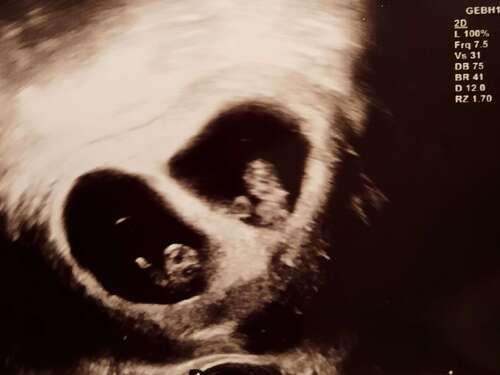

Ich bin in der 9. Woche. Durfte letzte Woche das Herz schlagen sehen und hören ❤️

Das war 6+5 man konnte den Herzschlag schon sehen 🥹😍und hoffe nächste Woche kommt das nächste

Unser Wunder bei 7+1 ❤️

7+5ssw🙃